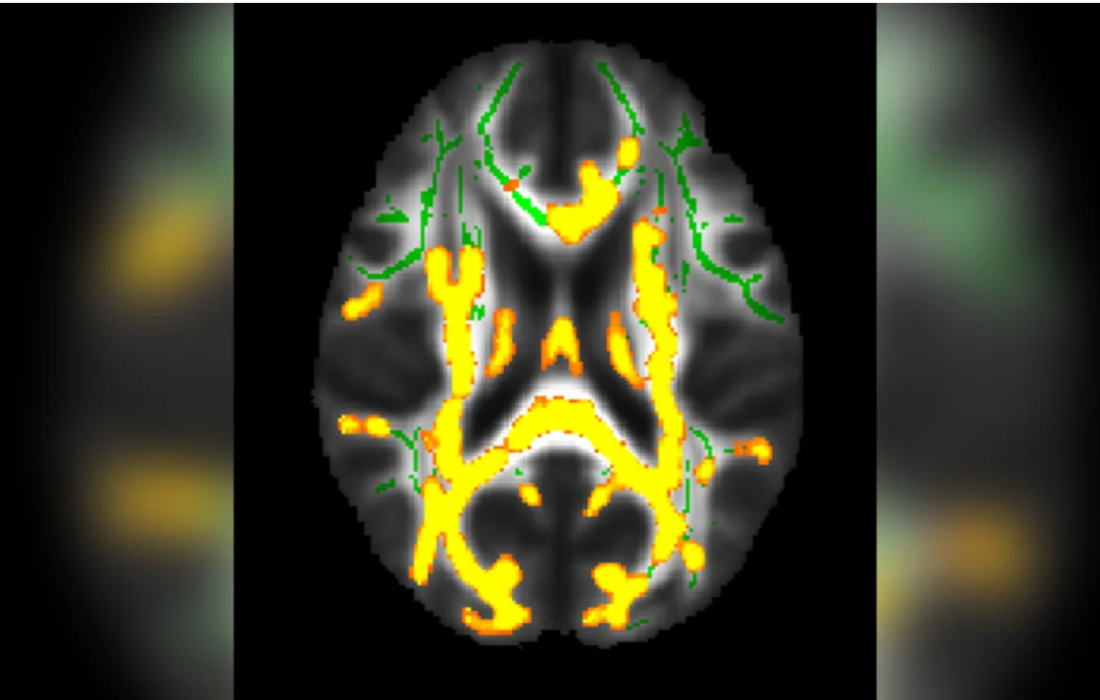

ماده خاکستری مغز حاوی اکثر سلول های مغزی می باشد که به بدن می گویند چه کاری انجام دهد. ماده سفید از الیافی تشکیل شده است که معمولاً در بستههایی به نام مجاری توزیع میشوند که اتصالات بین سلولهای مغز و بقیه سیستم عصبی را تشکیل میدهند.

افرادی که مقدار بیشتری از چربی موجود در ناحیه شکم را دارند، در مسیرهای وسیع ماده سفید مغز سطوح بیشتری از التهاب را نشان می دهند.

در صورت عدم وجود یک سیستم عملکردی مانند ماده سفید مغز، مغز قادر به ارتباط کافی با قسمتهای مختلف مغز و بدن نمیباشد. ماده سفید مغز مسئول ارتباط و ارسال اطلاعات بین نقاط مختلف مغز و همچنین بین مغز و سایر بخشهای بدن می باشد. بنابراین، برای عملکرد موثر مغز و ارتباط مناسب با بخشهای مختلف بدن، وجود یک ساختار مانند ماده سفید بسیار حیاتی می باشد.